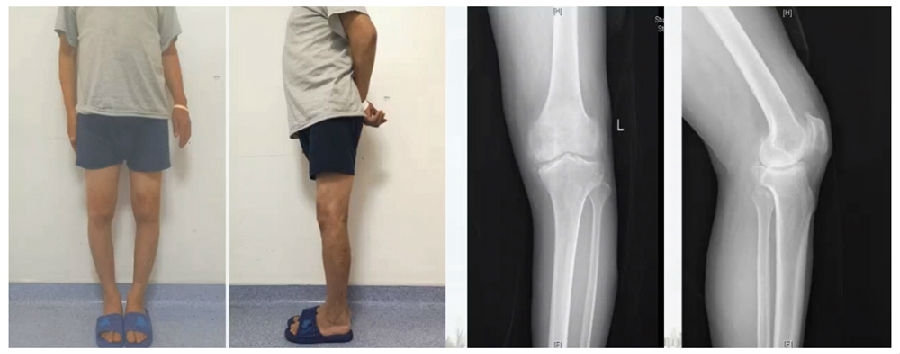

典型病例,女性,35岁,农民,左膝内翻、短缩、内旋。

术前

泰勒外固定架缓慢矫正短缩、内翻、前弓、内旋。

术中

该患者截骨后,做MAD矫正,目标MAD=0。患者术后1个月即达到设计的效果。

术后1个月